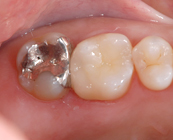

セラミックインレー

昔詰めた銀歯のお色が気になる方や金属アレルギーが心配な方へ

透明で美しく変色しにくい素材をおすすめします。見た目が天然歯に近い素材なので、区別がつきにくく年数がたっても変色しにくいことが特徴です。

Before

After